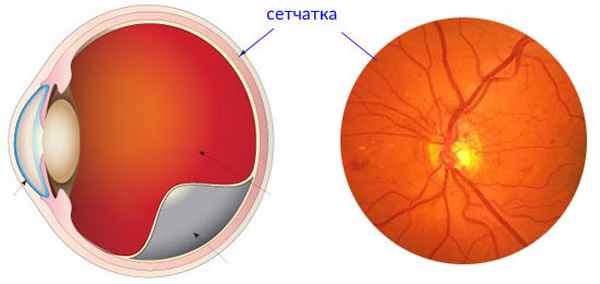

Изображения и анатомия сетчатки глаза

Раздел: Визуальный дайджест